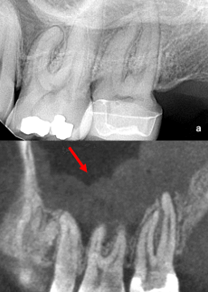

The normal mucosal lining within the maxillary sinus is <1 mm in thickness. Normal sinus mucosa is not visualized on radiographs. Sinus mucosal thickening more than 2 mm is an important indicator of pathology. CBCT imaging has proven to be a valuable resource to evaluate the correlation between apical periodontitis and the maxillary mucosa lining thickness (Fig 1).

5. Predictable and efficient root canal disinfection and treatment can heal sinus abnormalities (Fig 3).